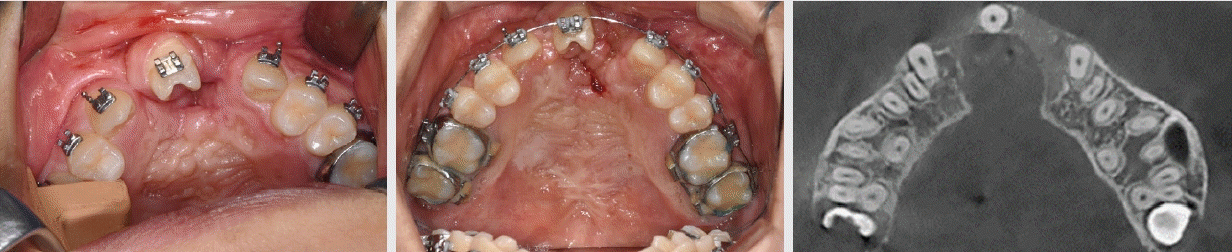

Figure 7.

Upper row: pre-surgical axial view, bone graft, and intra-oral photo

Lower row: 3 month follow-up axial view with new bone bridge, archform, and frontal view.

치과교정치료 이력이 없는 36세 성인 남성이 치과교정과로 의뢰되었다. 환자는 언어장애 2급 판정을 받았으며, 하악 좌측 대구치의 동통을 주소로 장애인 치료 센터를 내원하였다(Figure 2). 의과병력으로는 유아기에 구순열 및 구개열 관련 수술에 대한 가족의 진술이 있었다. 치료가 가능하지 않은 상악 좌측 제2 대구치와 하악 좌측 제1 및 제2 대구치 발치가 이루어졌고, 치주질환 및 치아 우식에 대한 치료가 진행되었다. 이어서, 하악 좌측 임플란트 식립과 2개월 뒤 이차 수술이 진행되었다. 이 시점에서, 상부 보철물 수복 공간이 부족하며 교합 및 치아위치 개선이 필요하다는 의견에 따라 치과교정과로 의뢰되었다.치과교정과로 의뢰되어 온 환자에게서 구순열 수술 이력을 확인할 수 있었고, CBCT 상의 Axial image에서는 상악 좌측 측절치의 결손과 치조열을 뚜렷하게 확인할 수 있었다. 상악궁 구강 내에서는 상악 우측 제2대구치의 발거, 상악 우측 제2소구치 결손, 상악 좌측 측절치의 결손 및 상악 좌측 유견치(또는 과잉치)의 잔존 치근이 관찰되었으며, 견치 후방에서 위치하였고 치아우식증에 이환 되어 있었다. 구강위생 관리에 대한 교육 및 보존적인 처치와 관리가 요구되었다. Lesser segment 인 좌측 소구치와 대구치의 악궁은 협설 방향으로 위축되어 전반적으로 람다 (λ) 형태의 상악궁 형태를 보였다.따라서, 구강악안면외과의 협진을 의뢰하여, 해당 잔존치근의 발거하였고, 치조골 이식술을 계획하였다. 구강외과 회신서는 "성장기 치조열 수술 시기를 놓치고... 매우 큰 편측성 구순구개열로...., palatoplasty, alveolar bone graftdhk cleft palate 수술 동반 예정 "이라고 하였다. 그리고, 골이식을 위하여 일차적인 치아의 배열을 요청하였다.Figure 4에서 관찰되듯이, 상악 우측 제2소구치와 좌측 측절치 결손을 동반한 치조열의 잔존과 구개열 수술의 결과로 인하여, 람다 (λ) 형태의 상악궁 형태는 상악과 하악의 횡적인 부조화를 야기시켰다. 이는 CBCT의 Coronal section상에서 확인되었듯이, 제1 대구치 위치의 양측성 구치부 반대교합으로 이어졌으며, 하악 좌측 구치부 임플란트의 크라운을 형성할 공간이 결여와 대합이 가능하지 않은 상황을 보여주고 있다. 구순구개열 환자의 포괄적인 진단과 치료 계획에 의한 치료의 아쉬움이 있지만, 하악 임플란트들이 최적의 위치에 식립 되었다는 전제 하에, 상악 제1 대구치 부위의 상악궁을 확장하여 횡적인 부조화를 개선할 것을 계획하였다.따라서, 전방의 골이식을 위한 확장 및 상악 제1 대구치 간의 폭경을 확장시키고자 Quadhelix를 장착하였고, 잠재적인 누공(fistula)의 확장을 최소화하기 위하여 천천히 조심스럽게 확장을 진행하였다. 상악 좌측 제2대구치는 오히려 폭경을 줄이기 위하여 Quadhelix 의 고리를 이용하여 악궁의 중심선 방향으로 견인하였다. 악궁 확장이 진행 과정에서, 필요한 경우에는 반대교합의 해소를 위하여 소구치 교합면 부위에 bite turbo를 적용하였다. 다행스럽게도 구개부의 누공(fistula)들이 확장되거나, 환자가 식사 시 불편감이 있다고 호소하지는 않았다. 상악 좌측 소구치에는 상악 제1대구치의 근심 회전을 막고자 부분적으로 최소한의 배열을 시도하였다(Figure 5).다음 단계로 전치부의 배열, 특히 상악 좌측 견치의 경사를 개선하고자 고정식 교정장치를 부착하고 microimplant를 활용하였다(Figure 6). Microimplant 고정원은 좌측 견치의 치축 개선, 소구치의 협측 이동, 구치부의 구개측 함입에 매우 유용하였다. 악궁의 형태는 삼각형에서 출발하여 점차 형태가 개선되었다 (Figure 6).상악 좌측 견치의 치축 개선을 위하여 greater segment에 대항하여 사용한 코일 스프링의 사용으로 인하여, 중절치의 우측 이동이 발생하였고, 하악 정중선과 일치하지 않은 상태이다. 더구나, 양측 상악 중절치는 6.5mm, 우측 측절치는 6.0mm의 폭경으로 일반적인 전치 폭경에 비해 왜소하다. 상악 좌측의 제2 대구치와 제2 소구치의 선천적 결손을 고려하면, 우측의 측절치 결손 부위는 임플란트 보철을 고려하는 것이 더 좋은 심미적 치료 대안이다. 중절치의 폭경이 평균보다 작고 보철과와 협진 하에 전치부 심미 보철과 임플란트 식립을 위한 재배열을 시행할 계획이다.악궁확장 및 악궁 배열 이후, 좌측 치조열과 전방 구개에 장골이식(iliac bone graft)을 시행하였고, 현재 양호하며, bone consolidation을 기다리고 있으며, 술후 6개월 이후 에 cleft 부위 골이식 공간에 임플란트 식립이 가능하다는 구강외과의 회신을 받았다(Figure 7).